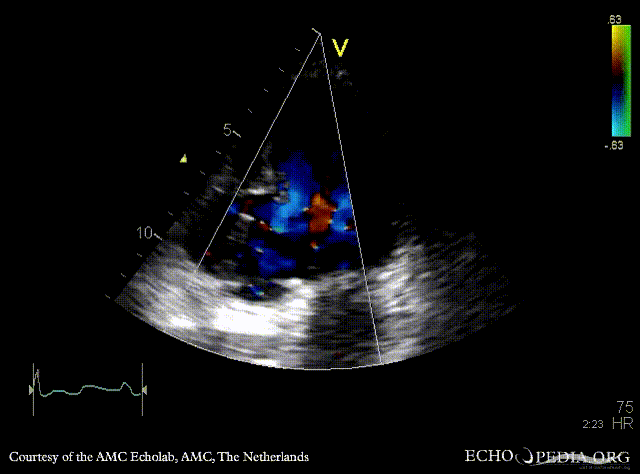

| A2CH: aneurysm of basal inferior wall | A2CH: Color Doppler |

| A4CH: aneurysm of basal inferior wall | |